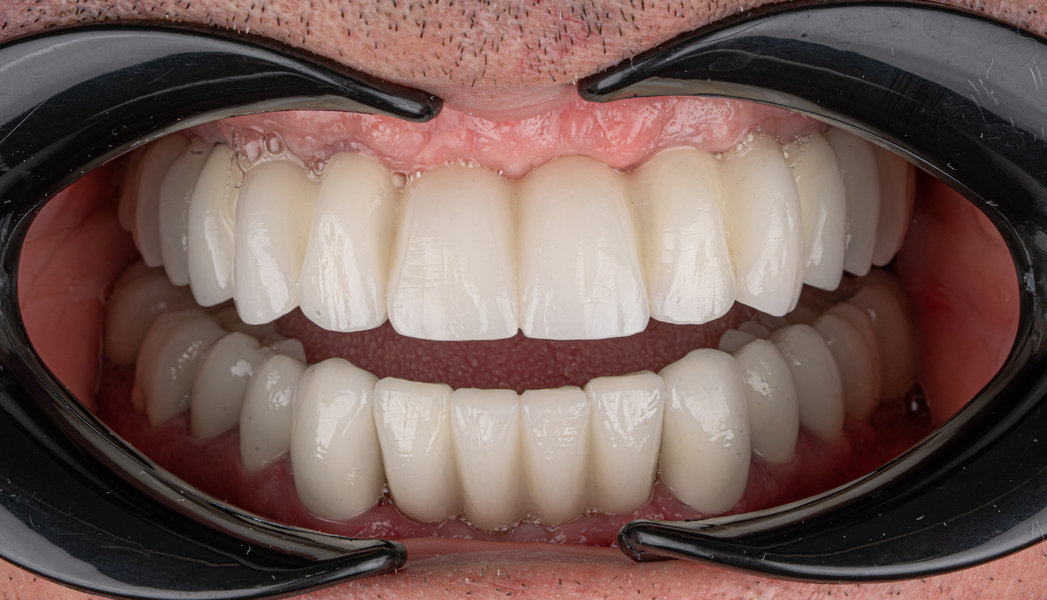

Caz 2